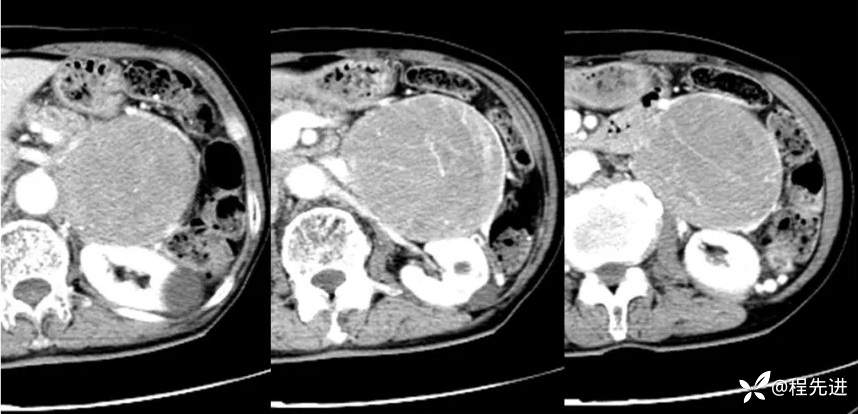

CT增强:

动脉晚期: